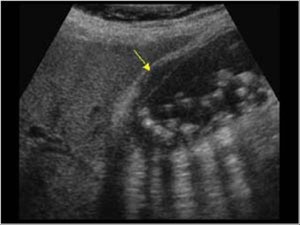

سۆنار: ئازمایشهکی زۆر باشه لۆ دیتنی بهرد و ههوی زراو و ههوی پهنکریاس ههتا بهردی ناو بۆری زراویش، بهس بهردی زراو که زۆر چووبیته خوارێ نزیک کونی زراو وریخهلۆک زهحمهت بە سۆنار دهبیندرێ